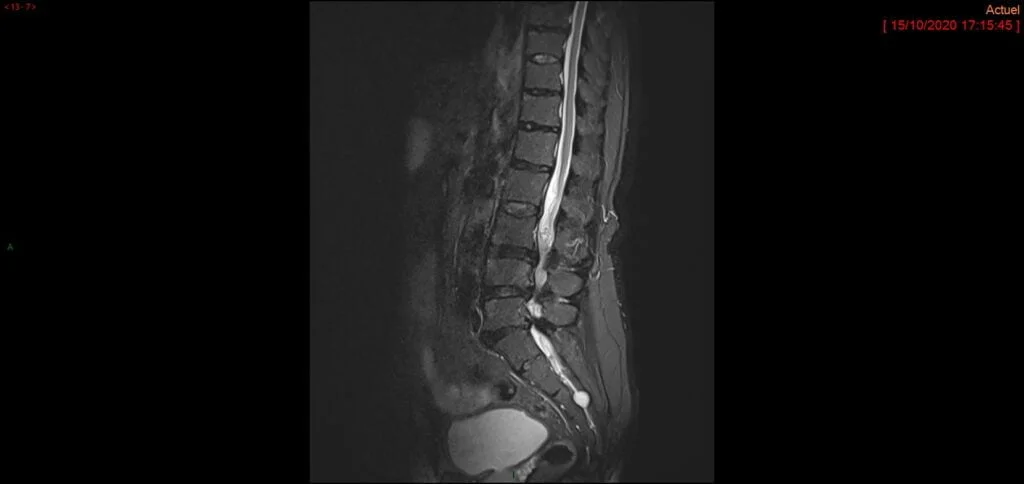

Les deux examens réalisés dans le bilan d’un canal lombaire étroit sont le scanner et l’IRM lombaires. L’IRM permet d’évaluer le degré de compression des nerfs et les niveaux vertébraux touchés. Elle évalue plus précisément la compression liée aux “tissus mous” (disques et ligaments). Le scanner va permettre d’obtenir des informations complémentaires sur la compression liée aux éléments osseux et sur une éventuelle instabilité sous-jacente de la colonne vertébrale. Pour compléter l’évaluation d’une potentielle instabilité, votre chirurgien pourra demander la réalisation de radiographies dites “dynamiques” prises dans différentes positions (flexion et extension).